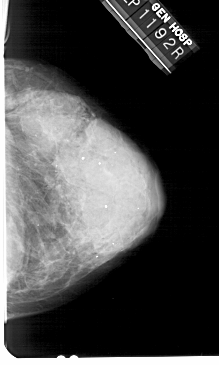

A_1936_1.RIGHT_MLO

RIGHT_MLO LINES 5491 PIXELS_PER_LINE 2911 BITS_PER_PIXEL 12 RESOLUTION 43.5 NON_OVERLAY